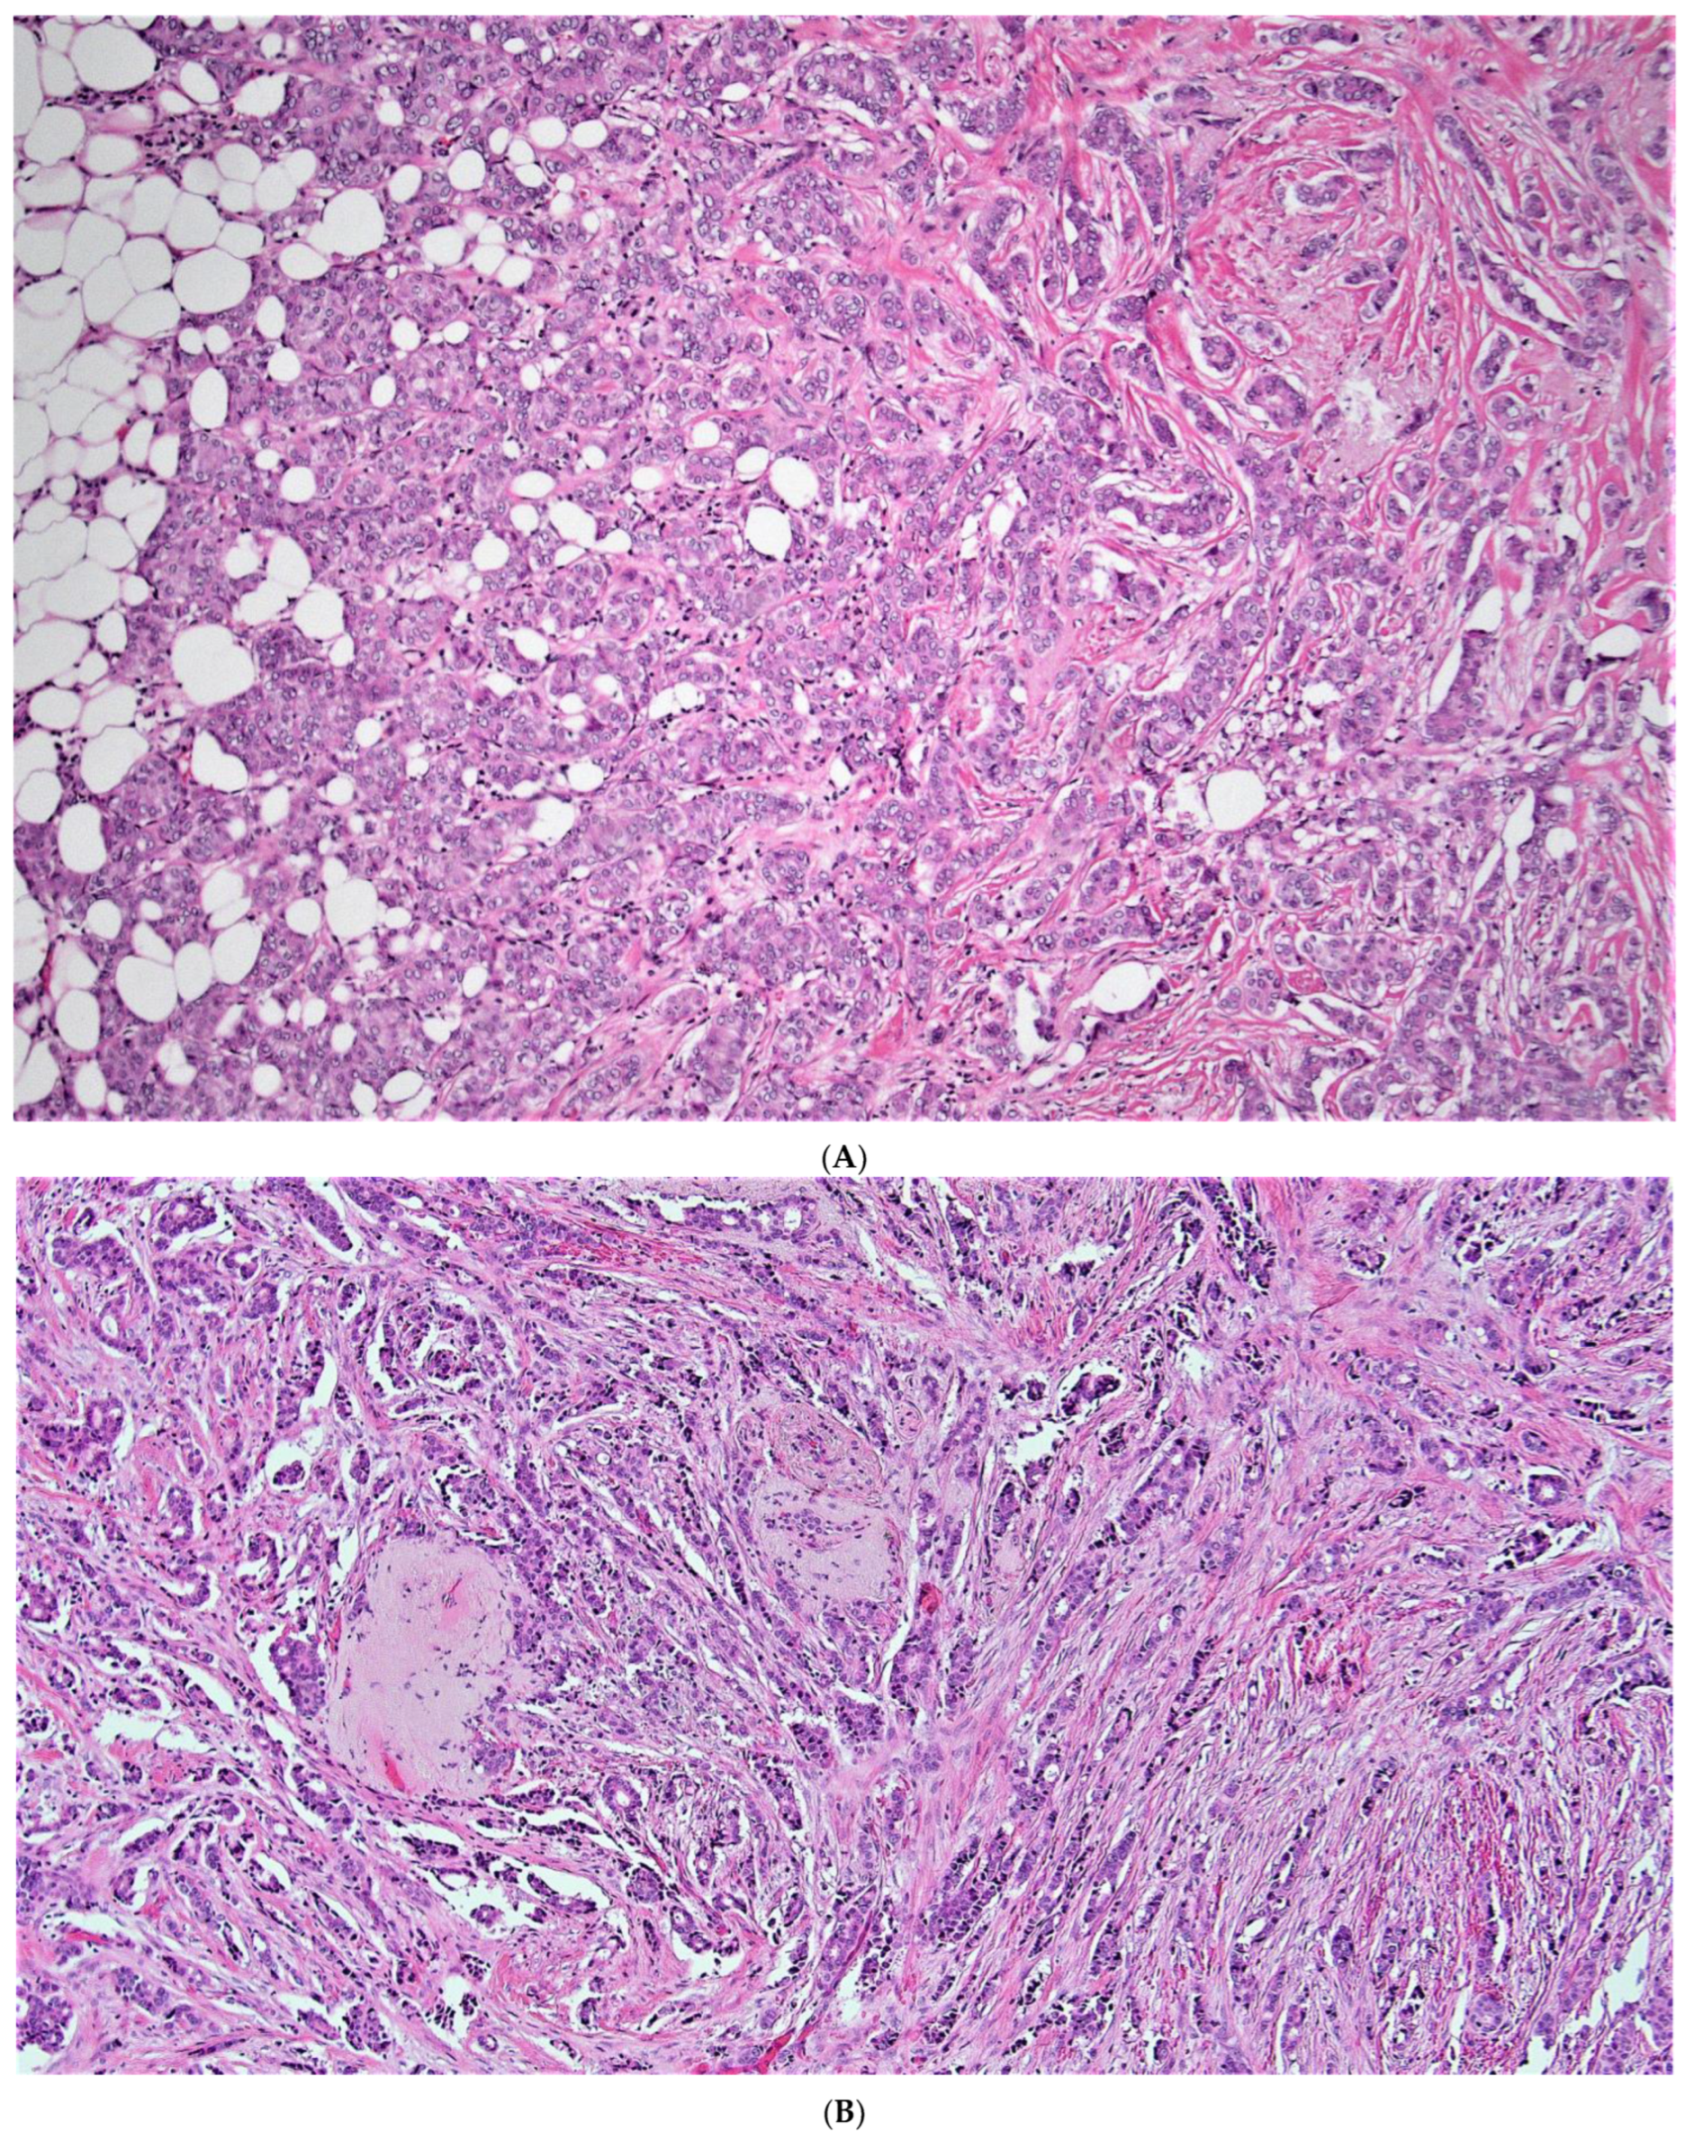

2. Materials and Methods

3. Results

4. Discussion